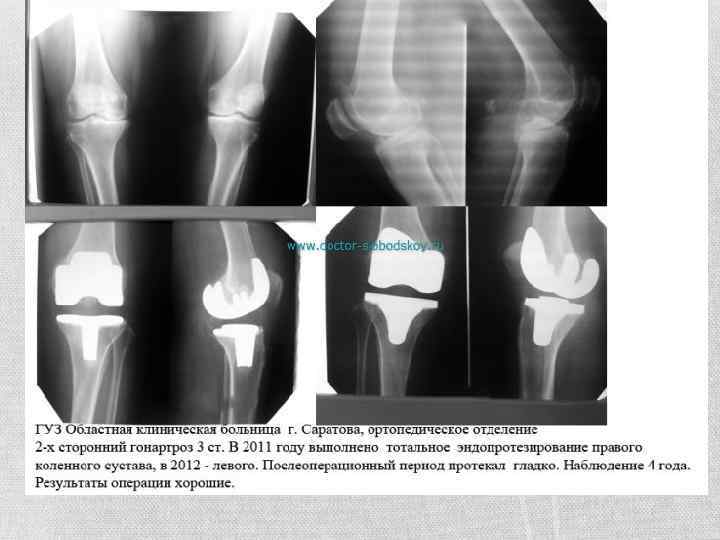

Хирургическое лечение Если же консервативное лечение не помогает, и тазобедренное сочленение продолжает разрушаться, то ситуацию исправит только хирургическое вмешательство – операция эндопротезирования.

Гонартроз • Гонартрозом или деформирующим артрозом коленного сустава называют дегенеративно-дистрофическую патологию, поражающую фрагмент хряща, который покрывает области бедренной и большеберцовой костей, образующих коленный сустав. • Гонартроз постоянно прогрессирует и приводит к постепенному поражению всего сустава, при этом происходит поражение кости с ее патологическим разрастанием и уплотнением. Все эти процессы затруднят нормальную ходьбу.